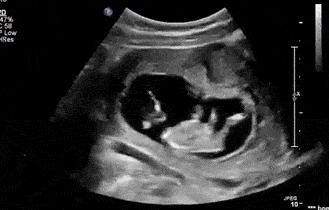

《孕前和孕期保健指南》建议孕妇在第三次孕检:20-24周时,进行系统超声筛查,就是我们俗称的“四维彩超”,大排畸筛查。

四维是高清动态的彩超,可以拍下胎儿的照片。但三维在筛查效果上,与四维并没有多大区别。

单胎建议孕24周做四维,双胎或多胎建议孕22周做四维。

四维不适宜过早或过晚做。过早做,胎儿小,看不清楚相关器官和肢体。太晚做,胎儿在体内长大了,不便于胎儿翻身让医生看到其他部位;同时,如果发现畸形,也耽误了治疗或处理的时间。

大排畸可以排除无脑儿、脑积水、肠道闭锁、肾积水、短肢畸形、部分先天性心脏病等。

但不能筛查:骨发育不良(需32周产科胎儿生长测量超声检查)、复杂心脏畸形、60%染色体疾病、智力、听力、视力的功能异常等。